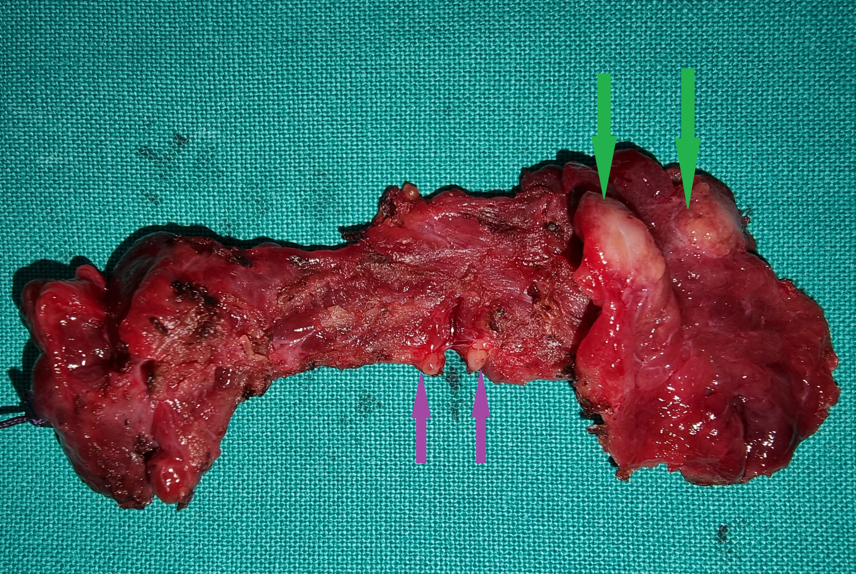

Total thyroidectomy surgical specimen. Green arrows — Papillary carcinoma. Purple arrows — Infiltrated microscopic lymph nodes of the isthmus (Courtesy Dr. V. Penopoulos)